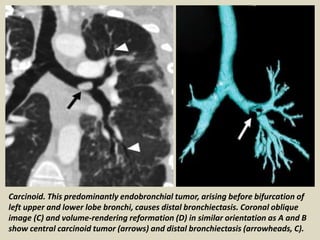

Carcinoid. This predominantly endobronchial tumor, arising before bifurcation

of left upper and lower lobe bronchi, causes distal bronchiectasis. Transverse

images of tumor (arrow, A) and distal bronchiectasis (arrows, B).

Carcinoid. This predominantly endobronchial tumor, arising before bifurcation of

left upper and lower lobe bronchi, causes distal bronchiectasis. Coronal oblique

image (C) and volume-rendering reformation (D) in similar orientation as A and B

show central carcinoid tumor (arrows) and distal bronchiectasis (arrowheads, C).